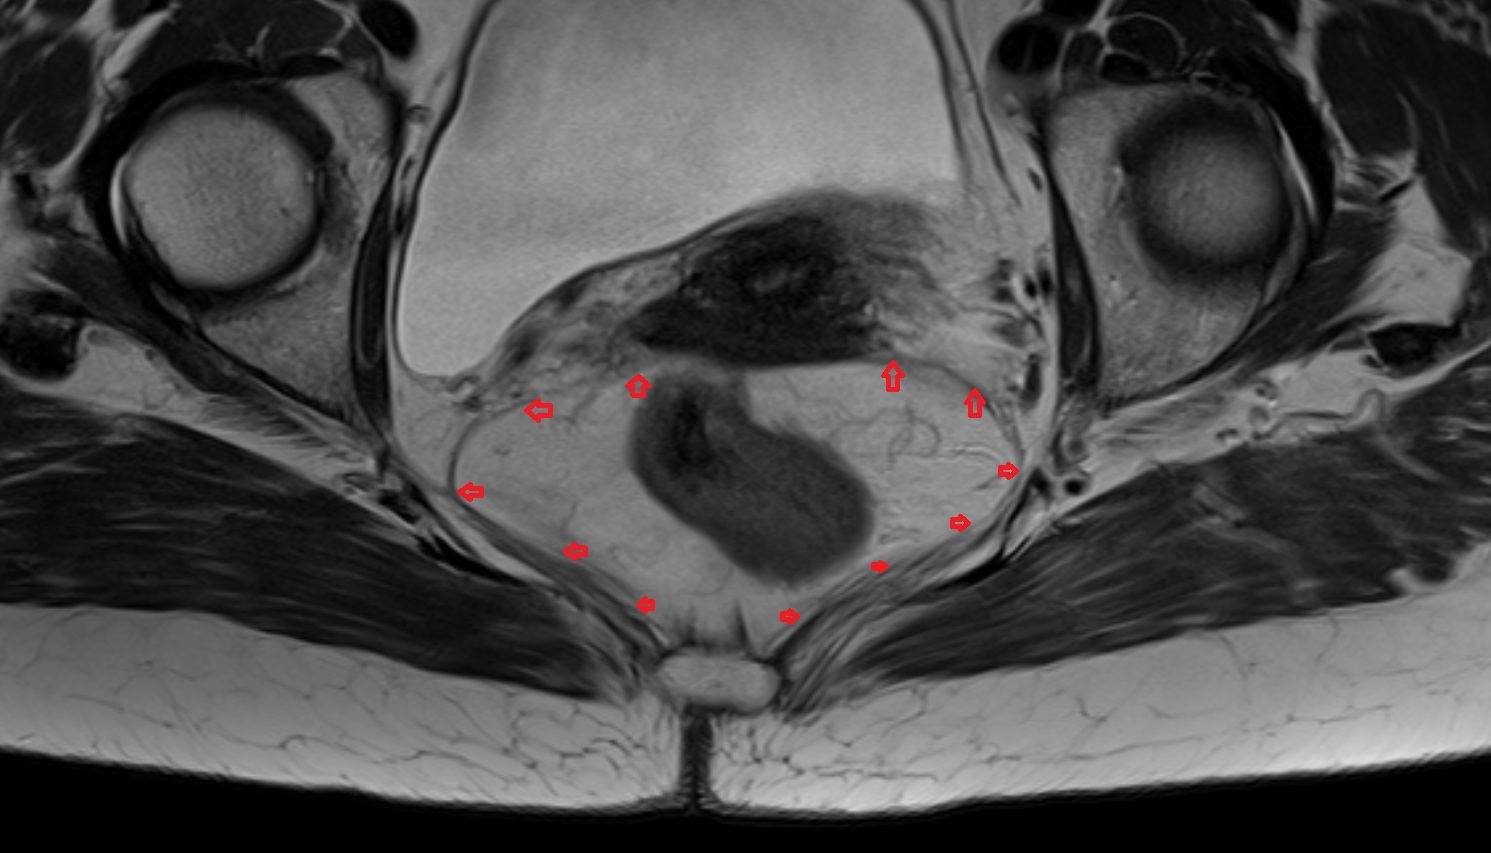

- Mesorectal fascia

- Mesorectum

- Rectum

- Uterus

- Vagina